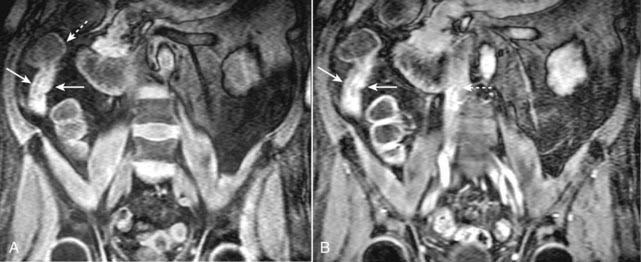

image

Figure 20-12 Active inflammation in Crohn disease.

A, Coronal T1-weighted fat-suppressed image from an MR enterography examination demonstrates thickening of the wall of the distal terminal ileum (solid white arrows). The adjacent cecum is normal (dotted white arrow). B, Coronal T1-weighted, fat-suppressed, gadolinium-enhanced image demonstrates marked enhancement of the wall of the terminal ileum (solid white arrows) indicating that this wall thickening represents active inflammatory narrowing of the lumen. Gadolinium is also seen within the inferior vena cava (dotted white arrow), a finding that helps us determine that this is an enhanced image.